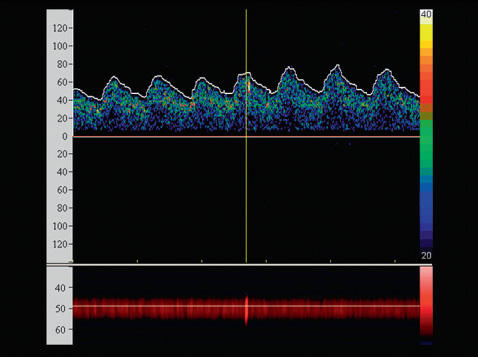

Fig 3

Embole enregistré par doppler transcrânien ipsilatéral à la sténose